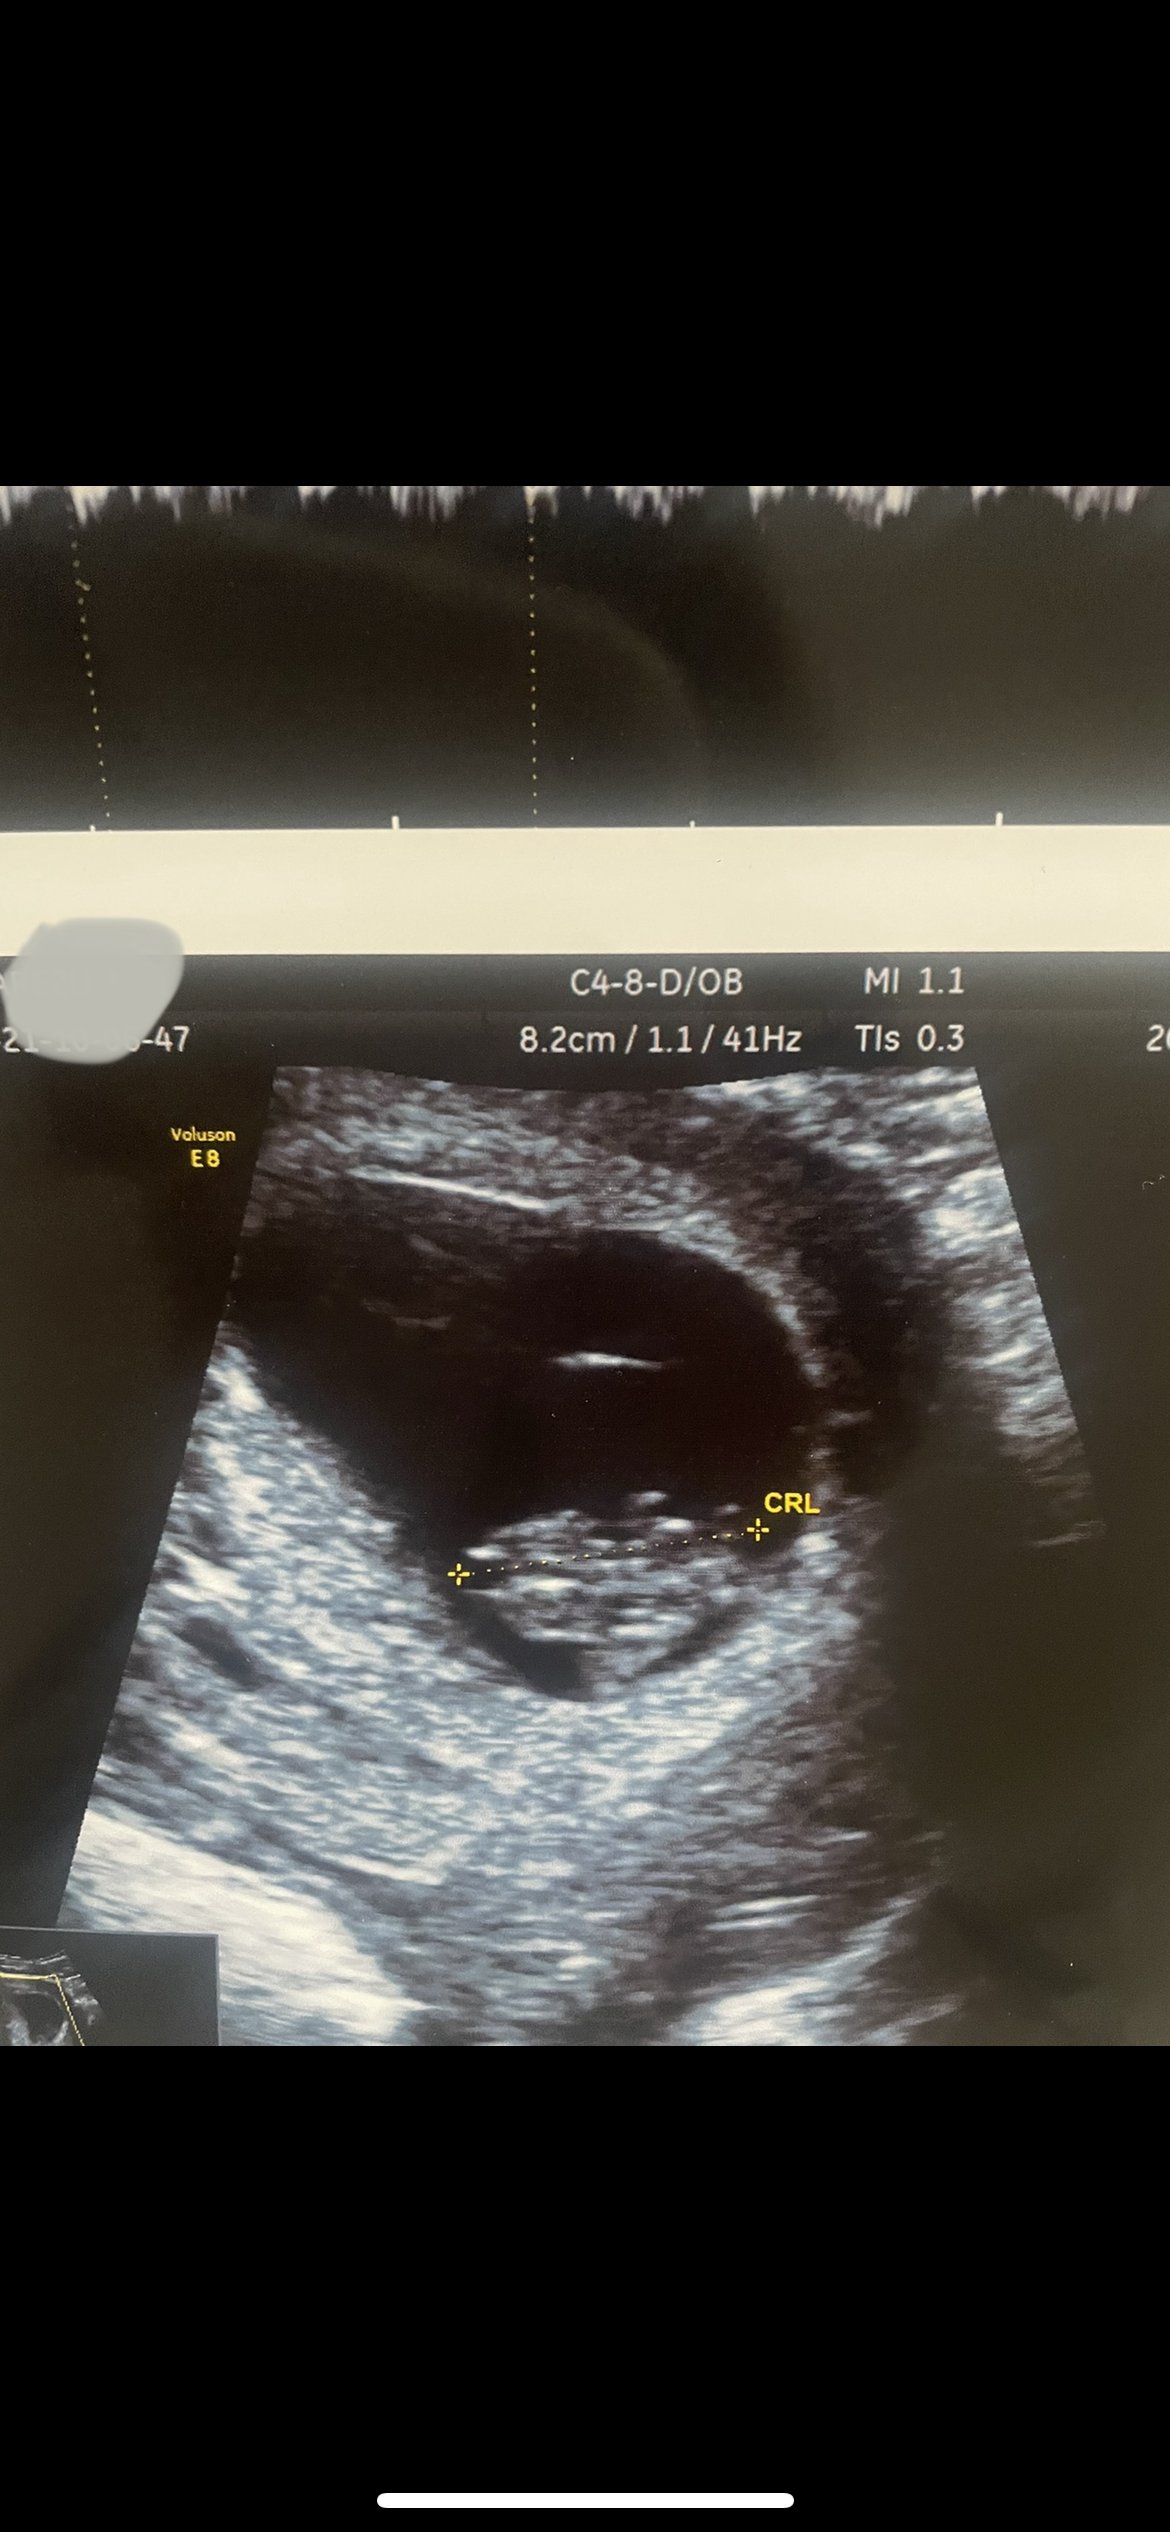

arezubanu مدیر استارتر عضویت: 1397/08/09 تعداد پست: 1581 عنوان بیاین از روی سونو بگین نی نی م چیه😍 597 بازدید | 59 پست توروخدا اگه بلدید نظرتون رو بگید میدونم خیلی کوچیکه ۸ هفته و یک روز بود توی سونوطبق موعدم هم دقیقا ۸ هفته میشدم 😍 1400/07/15 | 09:39 0 نفر لایک کرده اند ... گزارش تاپیک نامناسب

loveisdead عضویت: 1398/01/08 تعداد پست: 35524 سونو هشت هفته آخه چیش تشکیل شده که جنسیتش مشخص باشه آدمی که شمارو نصیحت میکنه در واقع داره با خودش تو گذشته صحبت میکنه🎭

banomah عضویت: 1400/05/08 تعداد پست: 1571 فعلا خیلی کوچیکه معلوم نمیشه ک عزیزم ترو هم بیخودی امیدوار نکنیم تو ۱۲هفتکی معلوم میشه کمی صبر کن😍 خدایا شکرتتتتت🥺😍😍😍